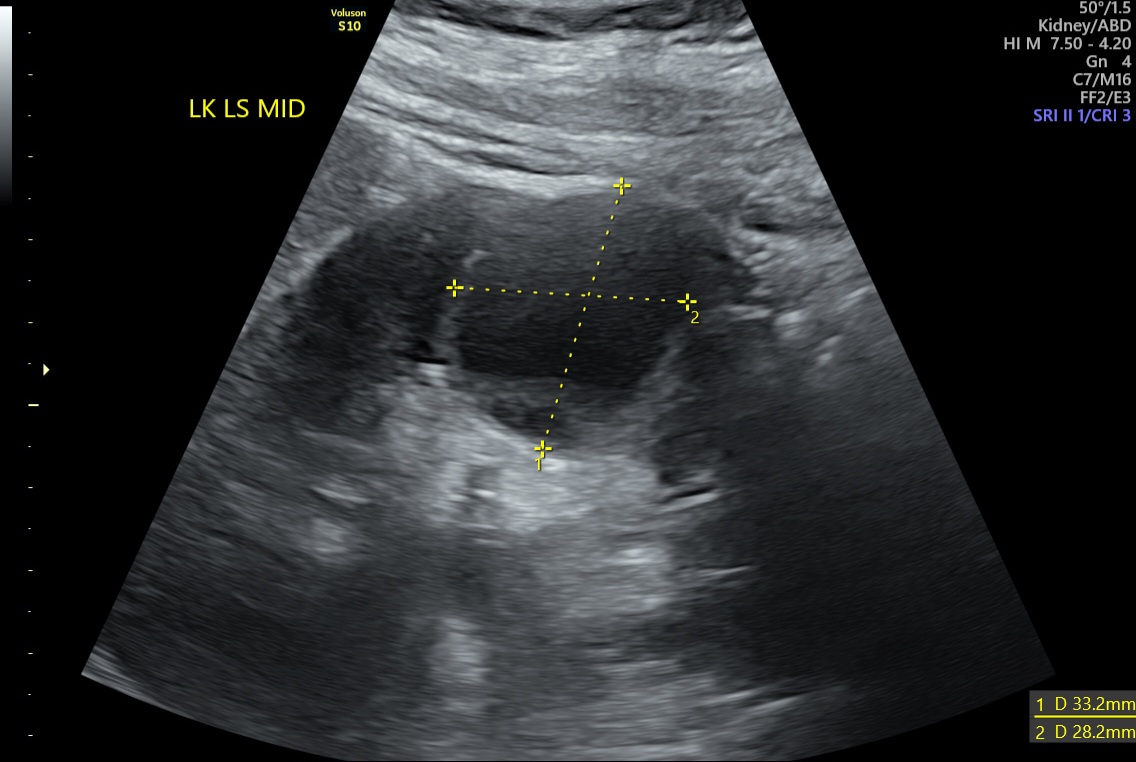

Czy mógłby ktoś mi powiedzieć czy 'infekcja cysty' to poprawna interpretacja załączonego USG?